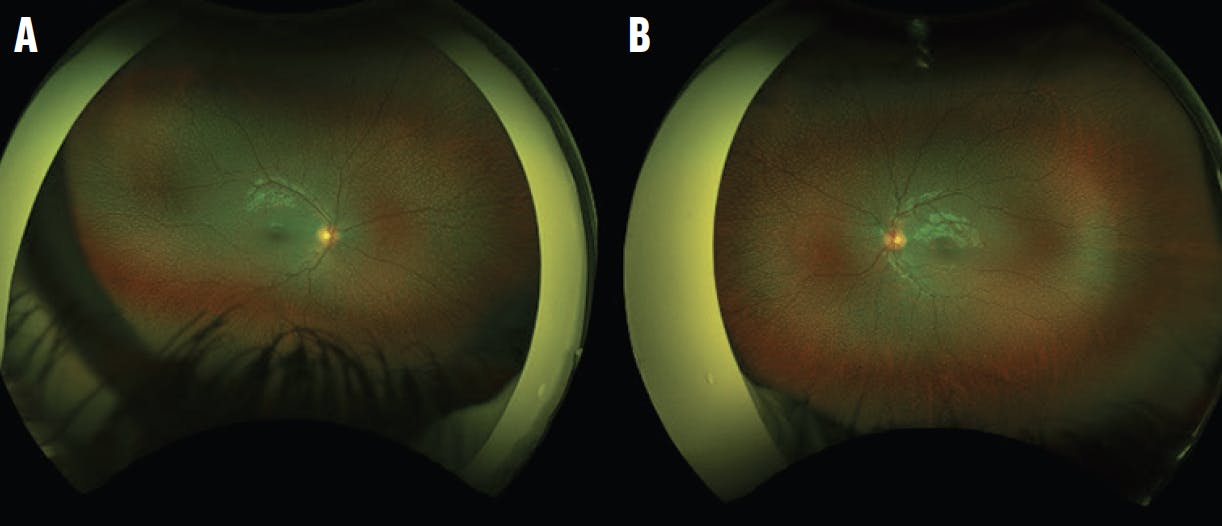

An 11-year-old boy with a history of microcephaly and developmental delay was referred for retinal screening. His VA was 20/40 in each eye. Fundus examination and widefield fluorescein angiography (FA) demonstrated avascular peripheral retina and geographic chorioretinal atrophy in the inferior midperiphery of each eye (Figure 1). OCT showed well-preserved inner and outer retina laminations in the central macula, but the outer retina became attenuated leading up to the inferior area of atrophy (Figure 2).

Figure 1. Widefield imaging of the right (A) and left (B) eyes shows peripheral avascular retina, retinal dragging, and midperipheral chorioretinal atrophy. Widefield FA of the right (C) and left (D) eyes highlights peripheral avascular retina and the chorioretinal atrophy. There is no neovascularization.